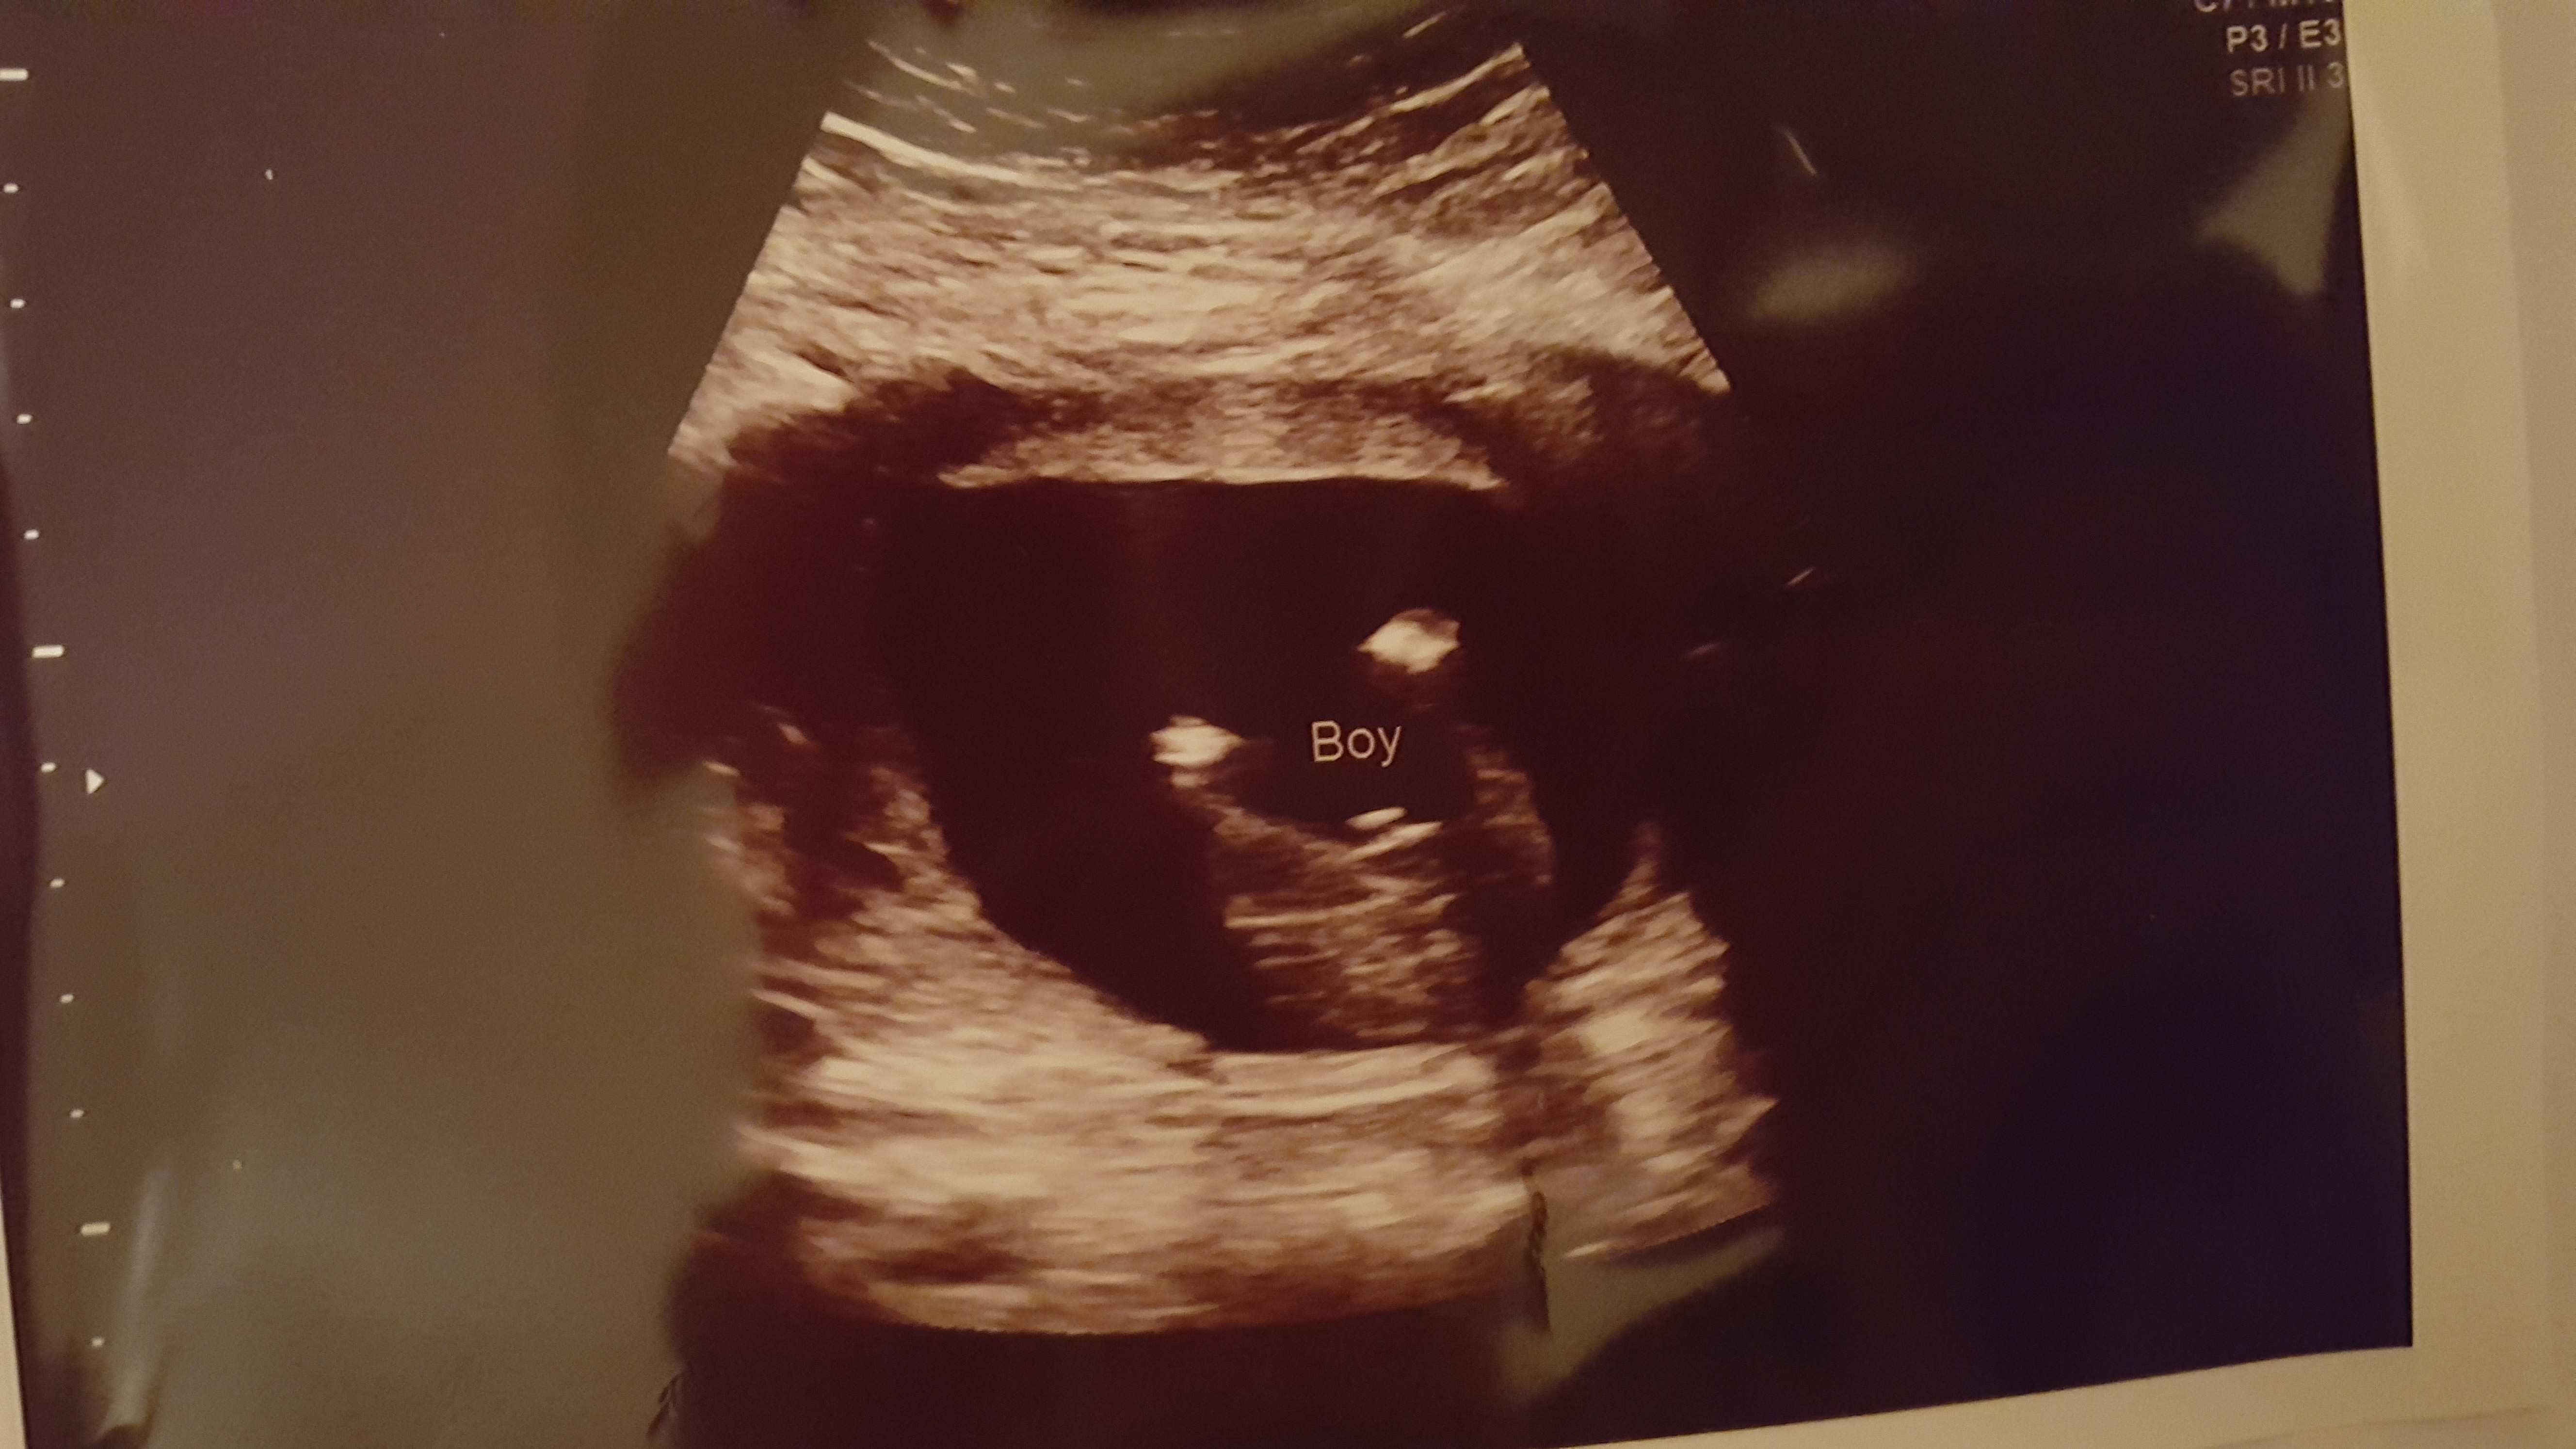

12 weeks 4 days.

Quite possibly a girl but it still could rise, I hope it's not some stacking I can see at the end and that you hear pink, good luck!

Possibly but still on the early side, good luck!x

Looks girly so far good luck!

Slight girl lean. As others have said, there looks to be some stacking on the end.

The nub is not entirely visible on this pic. More pics? Video?

Avril, top pic of your new pics looks very boyish, the leg may have been obscuring it in your other pics, hope I'm wrong:luck: I would have guessed girl off of your original pic also.

Sorry, that is a very boyish nub. I would be very surprised if this was a girl. So sorry you got all those girl guesses, I don't think that the straight line in the first pic is a nub, the nub is higher and hidden by the leg. Your second pic shows a perfect boy nub. Congrats with baby! :awe:

I would guess boy from the top photo in the 2nd lot of images. I'm sorry it probably isn't what you want to hear :(

With the new pics, the top one has a boy nub. Leaning boy now.